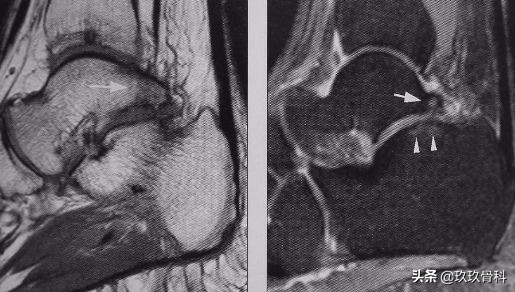

踝关节撞击综合征▲▲▲

1950 WOLIN首先描述踝关节内半月板样损伤。1991 ANDREWS确认上述损伤是因距腓前韧带撕裂后断端嵌入踝关节前外侧沟中形成,并报告切除这种损伤可缓解踝关节肿痛。

1991 FERKEL通过组织病理学分析证明其为增厚的滑膜组织。从此开始将踝关节无骨折脱位的长期肿痛称为踝关节软组织撞击综合征。

- 前外侧撞击综合征

- 前内侧撞击综合征

统称为踝关节软组织撞击综合征

- 踝前撞击综合征

以上三者统称为踝关节前方撞击综合征

体征:前内或前外间隙压痛;部分病人关节肿痛、背伸受限、不能下蹲。

诊断:踝关节扭伤史、X线无明显异常、踝前疼痛肿胀、经休息及非手术治疗不明显者应考虑为本病。

治疗:踝关节封闭—控制炎症;踝关节镜手术效果较好。